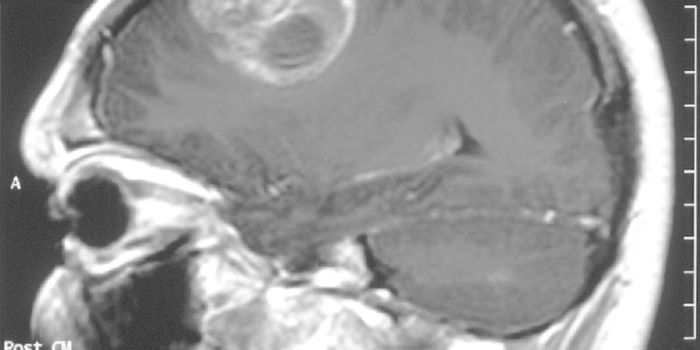

Read the latest articles about newly released neuroscience research and advances in experimental techniques. Topics include research news in neuroscience, neurology, psychology, brain science and cognitive sciences.